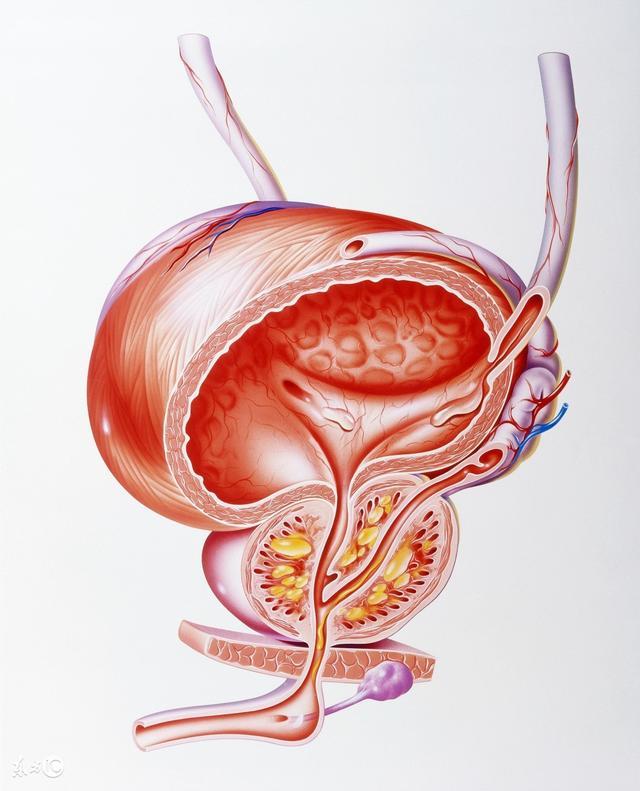

腹部、頸部青筋——肝病、心病 如果出現腹部青筋,說明是比較嚴重的積滯,往往是較難治的疾病,如肝硬化腹水、腫瘤後期等。脖子上持續有青筋凸起,說明兩種情況,一是心功能不全,多見於肺心病等疾病;二是心包炎或心包積液。 調理方法:如果這兩個部位出現青筋,則需要引起重視,及時就醫,切勿通過其他方法緩解症狀,以致延誤最佳的治療時機。